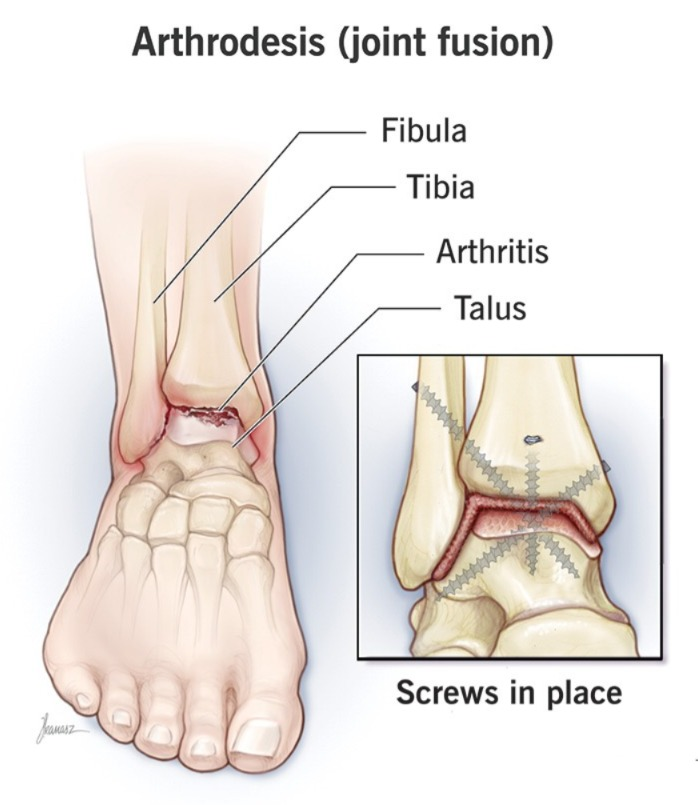

15)Define arthrodesis. (આર્થ્રોડેસિસ ને વ્યાખ્યાયિત કરો).

• આમાં જોઈન્ટ નું સર્જિકલી ફ્યુઝન કરવામાં આવે છે.